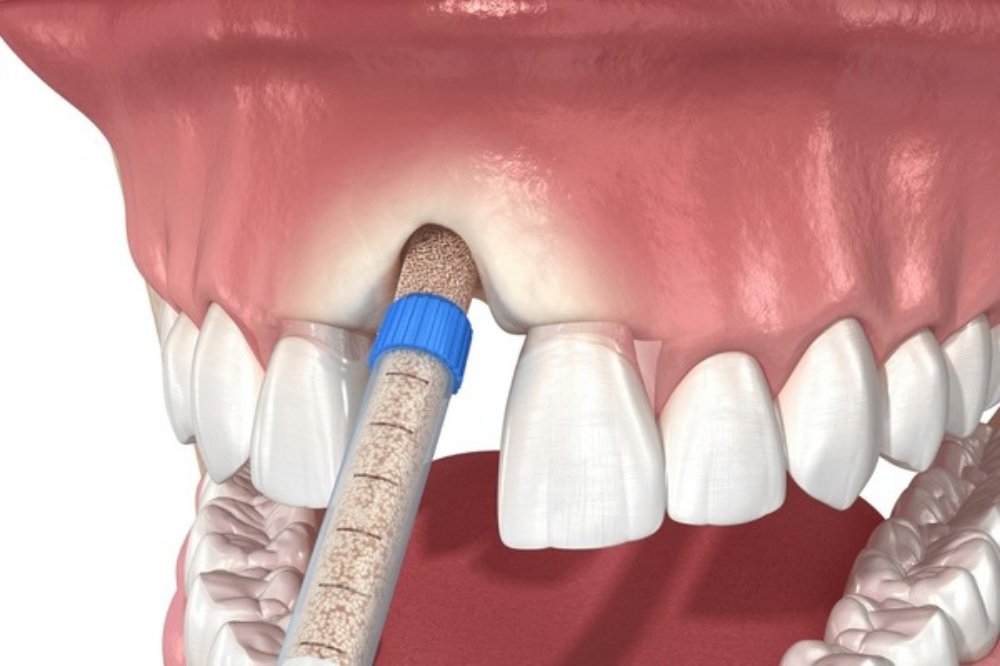

What is Sinus Lift Surgery?

A sinus lift is a dental procedure that adds bone to the upper jaw, near the molars and premolars. This is often needed before placing dental implants when there is not enough bone.

- The sinus is gently lifted upward.

- Bone material is added below it.

- This creates a strong base for implants.

This procedure helps improve long-term implant success and restores proper chewing function.